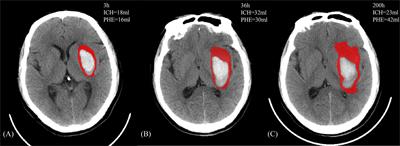

The association between blood pressure variability and perihematomal edema after spontaneous intracerebral hemorrhage